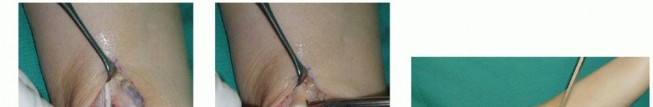

The patient is positioned supine (

FIG 3

).

For a lateral OLT, a bolster under the ipsilateral hip typically affords better access to the lateral talar dome. We routinely use a thigh tourniquet.

FIG 3 • Positioning is supine, with easy access to the medial ankle but without too much external rotation, which would make access to the lateral knee cumbersome.

*